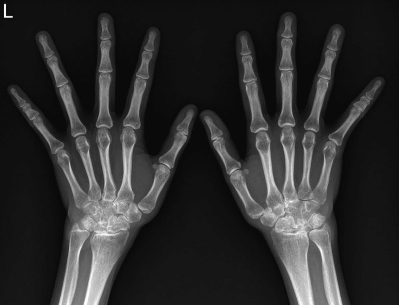

血液所見:赤血球 430 万、Hb 12.5 g/dL、Ht 38 %、白血球 8,300、血小板 23 万。血液生化学所見:AST 14 U/L、ALT 18 U/L、LD 204 U/L(基準 176〜353)、ALP 258 U/L(基準 115〜359)、尿素窒素 10 mg/dL、クレアチニン 0.5 mg/dL。免疫血清学所見:CRP 3.1 mg/dL、リウマトイド因子<RF>72 IU/mL(基準 20 未満)、抗 CCP 抗体 151 U/mL(基準 4.5 未満)。B型とC型の肝炎ウイルス検査および結核菌特異的全血インターフェロン γ 遊離測定法<IGRA>は陰性である。胸部エックス線写真で異常を認めない。両手エックス線写真を別に示す。

両側手関節および両側示指と中指の中手指節関節に腫脹と圧痛とを認める。皮疹は認めない。